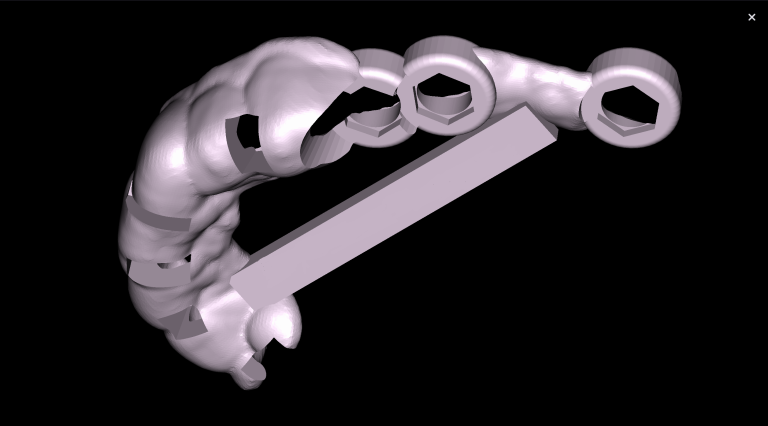

Solution: The automated process of segmentation and formation of 3D models from DICOM files allows extracting individual structures for subsequent 3D printing. The printed model of the third molar, taken from the “STL” module of Diagnocat, is used to prepare the socket for the transplanted tooth. The 3D reconstruction generated using Diagnocat displays the structure of the jaws and teeth and enables the visualization of tooth 37 (Universal 18) with periapical lesion around the roots. In this case, Diagnocat serves as a communication tool that helps convince the patient of the importance of timely implementation of the proposed treatment plan.